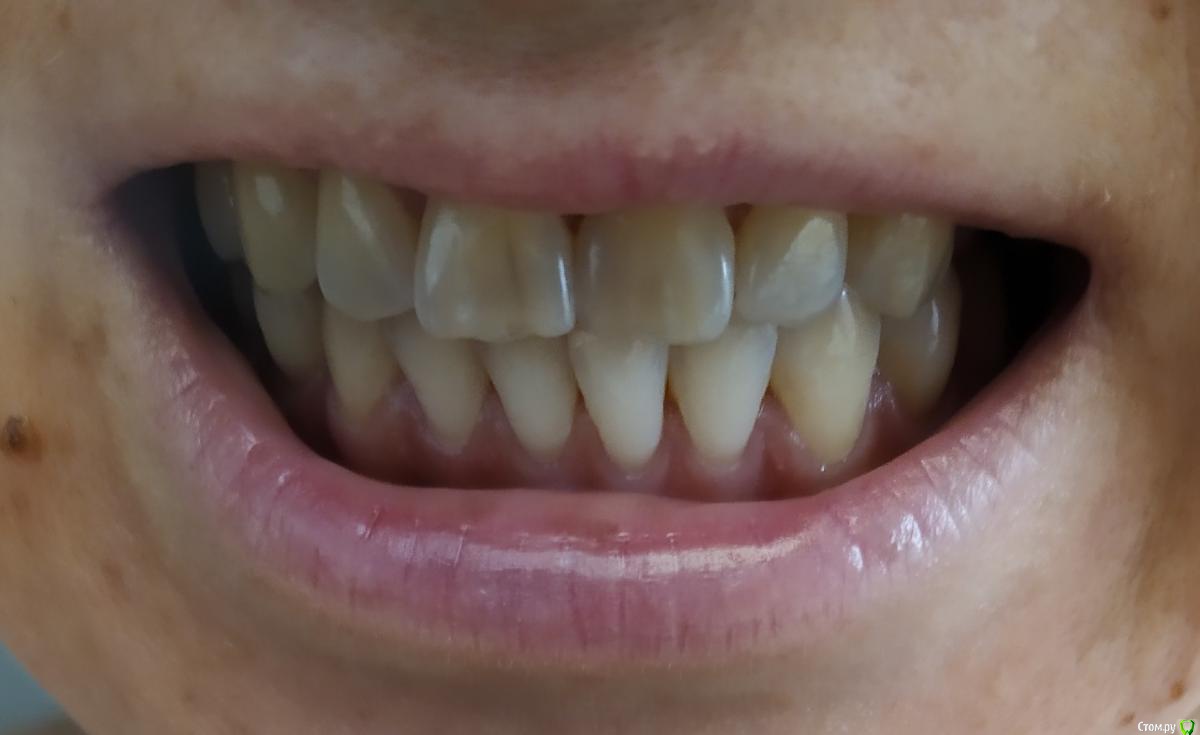

Все началось с того, что в 10 лет я поняла, что при улыбке у меня не поднимается верхняя губа и верхние зубы не видно, ну может на 1 мм. Так я ходила 20 лет с комплексом улыбки. А в 30, попав к новому стоматологу, врач предложила мне сделать художественные реставрации и удлинить верхние зубы. И тут началось.

Нельзя удлинить левый верхний, потому что нижние пошли а наклон, и он упирается в левый нижний.

1 ортодонт сказала, что все вообще отлично, а нижние подровнять реставрациями.

2 ортодонт сказала, что просто ставим брекеты и все за 8 месяцев приводим в норму.